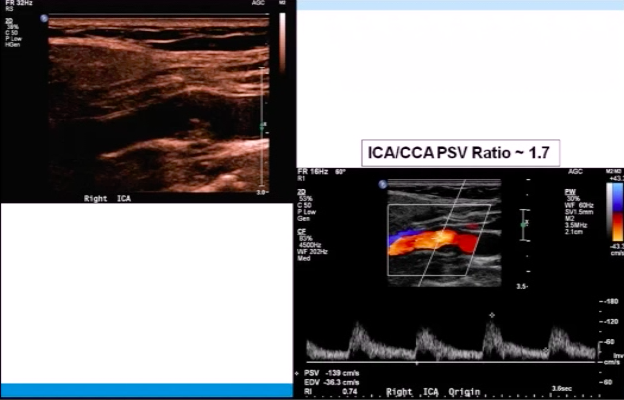

Patient has Lt ICA 100% occlusion. Rt carotid system shown below. PSV = 208 cm/s in proximal Rt ICA.

Most likely diagnosis?

mild Rt ICA stenosis (<50%)

since Lt ICA is 100% occluded, there should be elevated Rt CCA velocities (CCFA*)

plaque in proximal Rt ICA is <<50% ⇒ elevated velocities across Rt ICA are likely due to CCFA

*CCFA = compensatory carotid flow augmentation